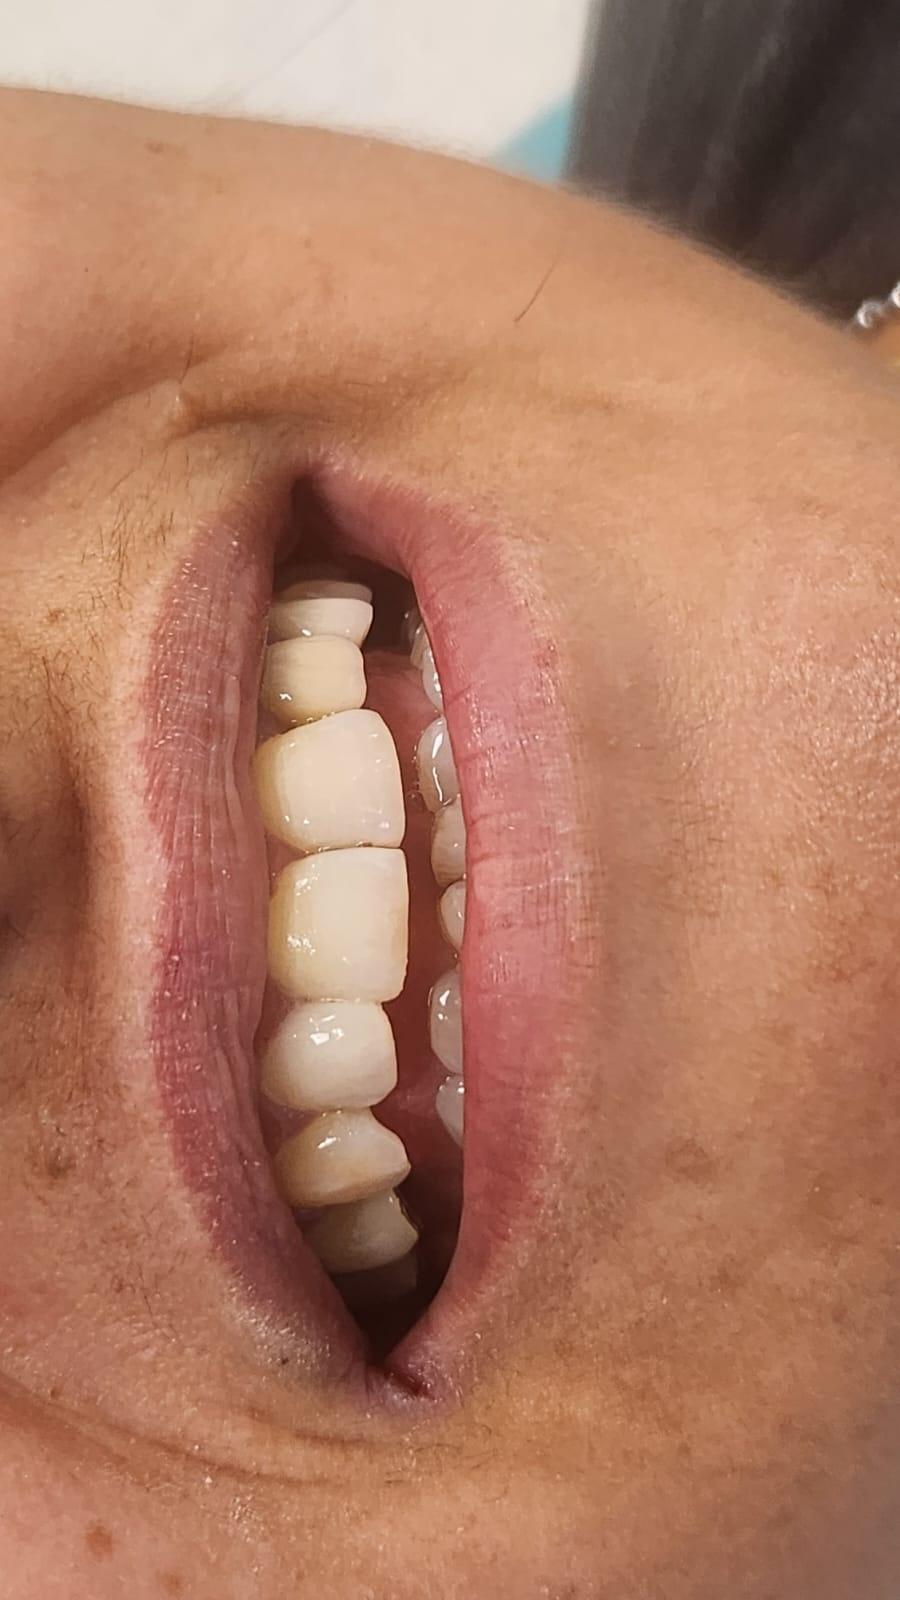

Clinica LUY ESTHETIC ART defineste parodontoza ca fiind rezultatul direct al placii dentare, care se depune pe suprafata dintilor, dar si in apropiere de marginea gingivala. Aceasta boala duce la pierderea dintilor, chiar daca ei sunt aparent sanatosi si nu prezinta carii. Edentatiile, afecteaza vorbirea, aspectul, dar si capacitatea de a mesteca.

Boala parodontala are un caracter progresiv. Pentru cazurile mai grave, recomandam tratamentul parodontal chirurgical rezectiv sau regenerativ.